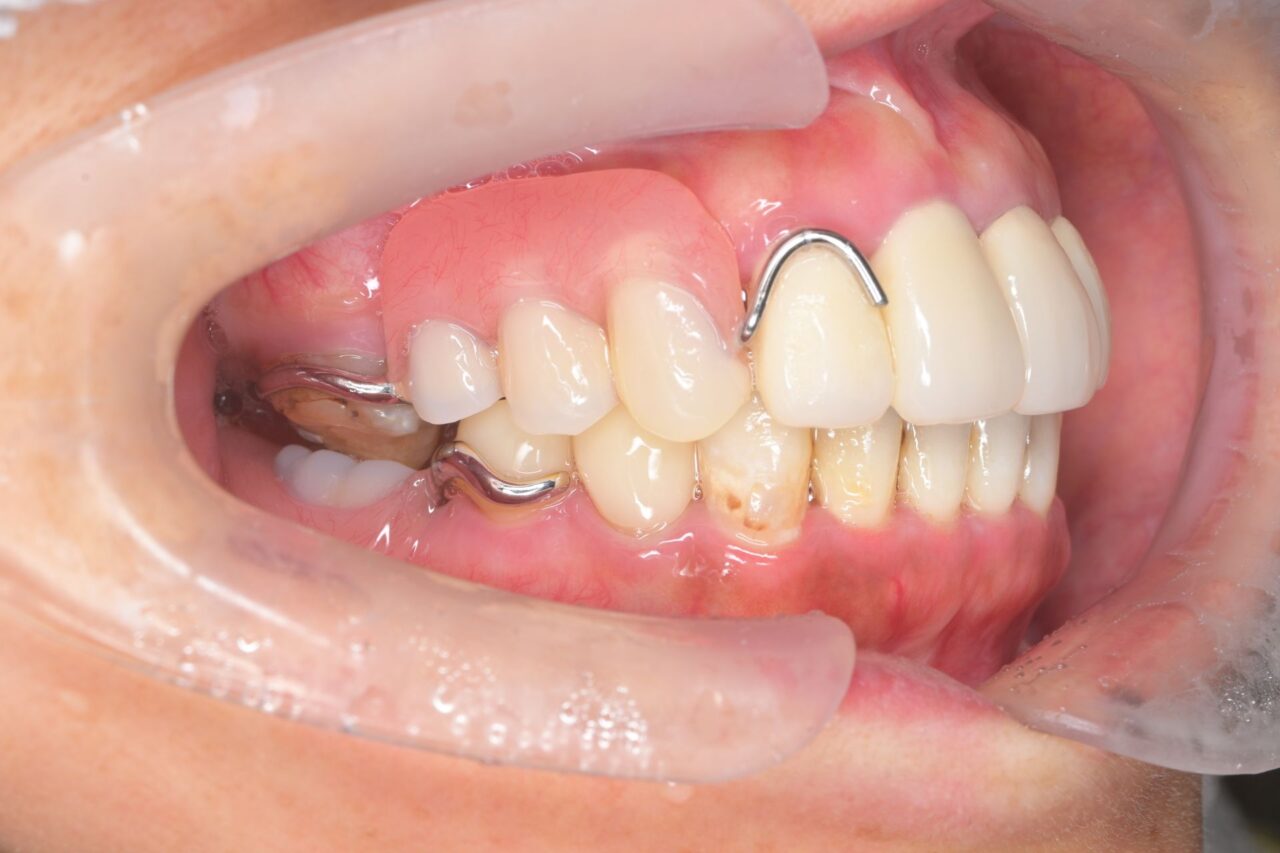

右側面

奥歯がありません。前歯があるので不格好にはならないのですが、奥歯=大黒柱が無い状態です。奥歯が無いことによって、かみ合わせが深くなってしまい、顎関節にも負担がかかっている状況です。